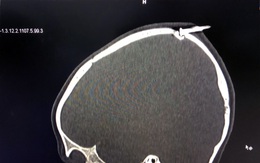

Bé trai 2 tuổi bị té, đinh sắt đâm lún xương sọ

Trong lúc chơi đùa, bé trai 2 tuổi không may té ngã, bị cây đinh dài 3cm ở cạnh giường đâm vào đầu làm lún xương sọ.